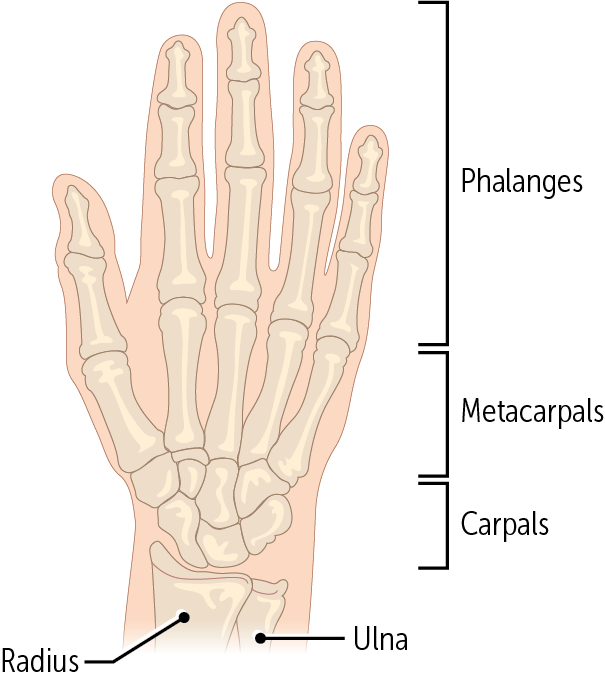

The hand comprises__ bones: __ carpal bones, __ metacarpal, and __ phalangeal bones

27, 8, 5, 14

Every digit is made up of a metacarpal bone and three phalanges, except for the ___________, which only has two phalanges.

thumb (aka the pollux - Latin for thumb)

The metacarpals are the most proximal bones of the digits (Figure 14). These bones—numbered 1 through 5, with 1 being the _____—connect the carpals to the proximal phalanges

thumb

________ are the longest bones in the hands. They have a base, body, and head; like the ulna, their head is distal and their base is proximal.

The metacarpals

Every finger has three phalanges (proximal, medial, and distal) except for the _____, which only has two (the proximal and distal).

thumb